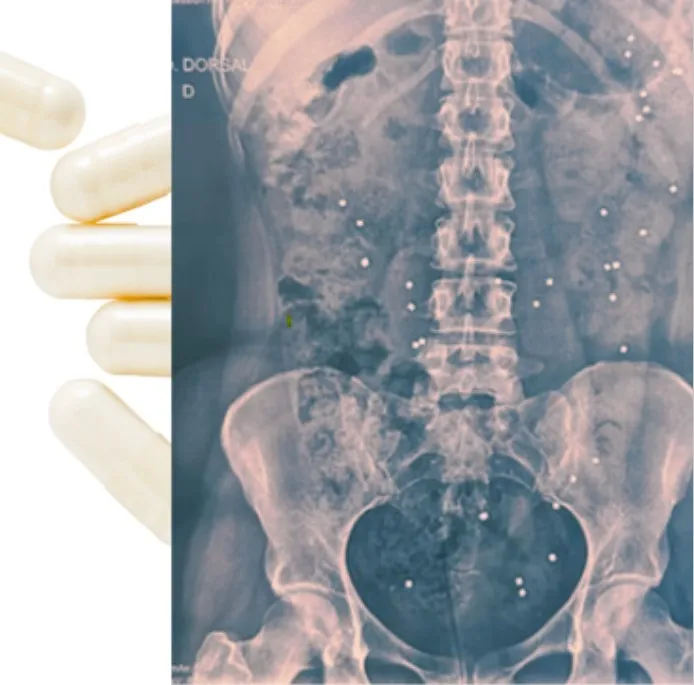

• Estudo do tempo de transito do cólon

Tempo de transito do cólon